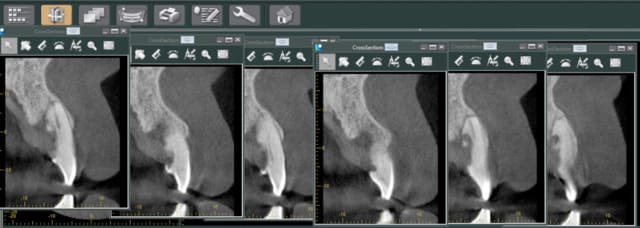

resorption interne.

extraction curetage, pose d'un bloc biobank cortico-spongieux et poudre d'os biobank, membrane at collagene et patch palatin pour fermer le lambeau.